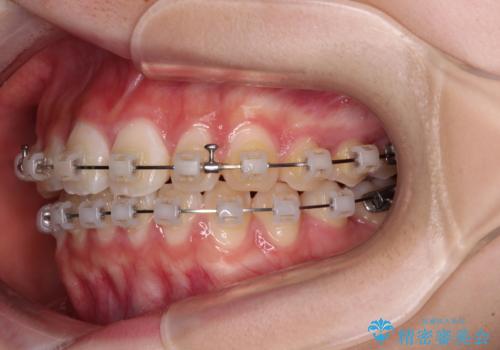

- 矯正装置

- クリアブラケット

- 上下前歯のねじれを気にして来院された患者様です。

ワイヤー矯正でもマウスピース矯正でも対応可能でしたが、マウスピース矯正の自己管理が面倒であること、上顎前歯の捻転が著しいことから、ワイヤー矯正での治療を希望されました。